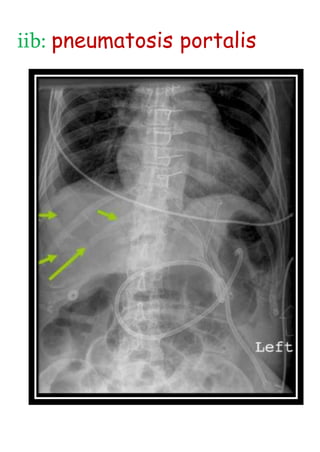

iib: pneumatosis portalis

NECROTISING ENTEROCOLITIS Stage 2Definite NEC Air enters intestinal wall Divided into - iia: pneumatosis intestinalis AIR IN WALL AIR IN LUMEN

• 16.